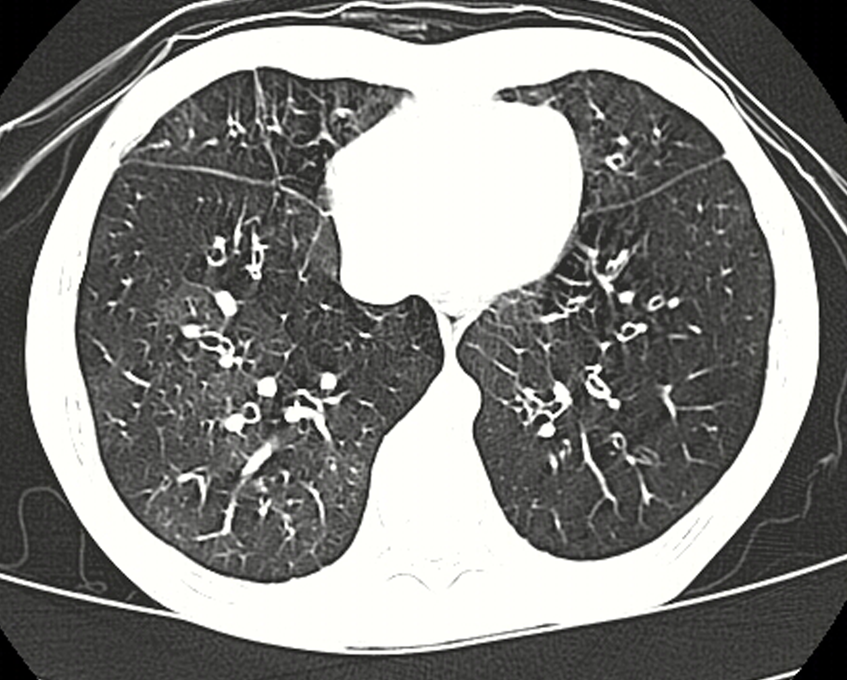

Bronquiolitis es una infección pulmonar que es muy común en niños pequeños y bebés. Regularmente suele causar inflamación y congestión de las pequeñas vías respiratorias es decir los bronquiolos del pulmón. Enfermedad es más común en los niños que los adultos.

Regularmente esta enfermedad la causa un virus y se suele presentar frecuentemente durante los meses de invierno. Si te interesa aprender más de esta enfermedad o crees que la puedes padecer sigue leyendo porque aquí te vamos a contar sobre sus síntomas y tratamientos comunes.